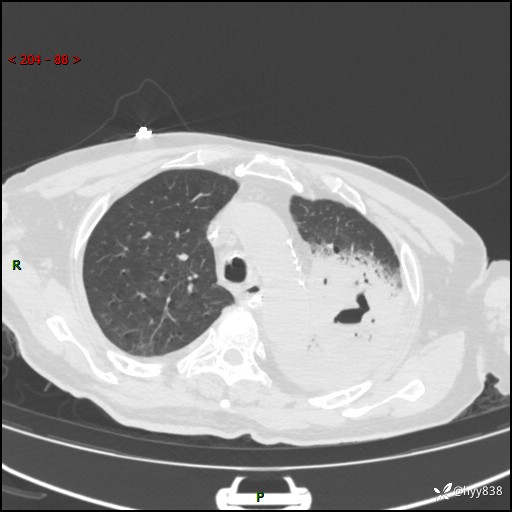

胸部CT复查(2024.8.5)